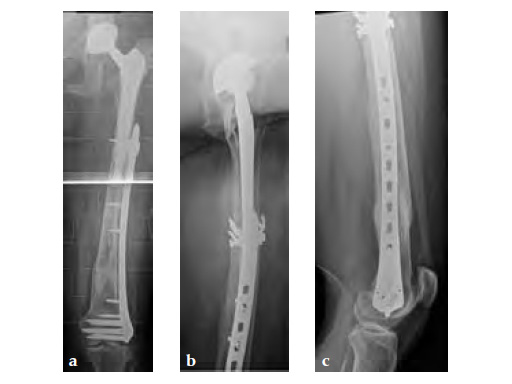

Case 1: A 78-year-old female sustained a periprosthetic fracture, Vancouver type C, 9 years after a total hip arthroplasty.

Case 2: A 76-year-old female with a Vancouver type C fracture.